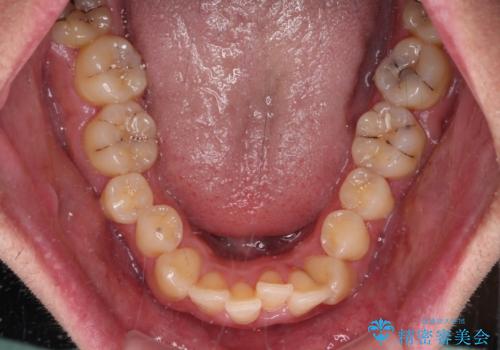

- デコボコと前歯の突出感を気にして来院された患者様です。

舌の突出癖などにより上顎前歯が前方に突出し、さらに歯列幅が狭小になっている状態でした。

また、上顎歯列全体が下顎に対して前方位に位置していました。